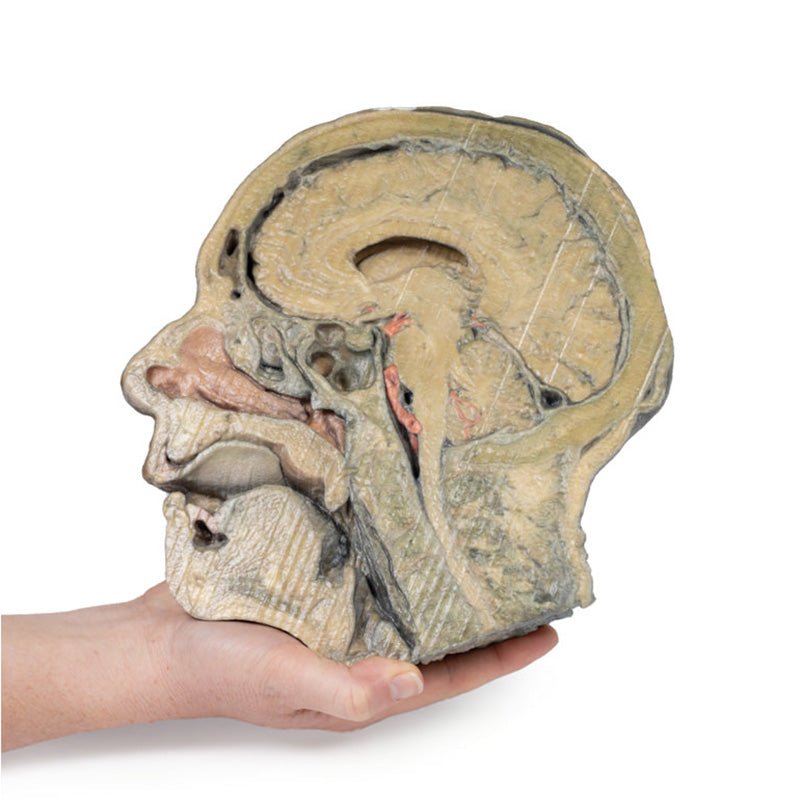

In the preserved midsagittal section there is preservation of the endocranial

contents, the nasal and oral cavities, and the pharynx to the level of the

laryngeal cartilages. The nasal cavity is preserved nearly intact, except for a

small window excised into the middle nasal concha to expose the ethmoid

air cells. A very large sphenoid sinus exists in the individual just superior

to the torus of the auditory tube in the nasopharynx. The oral cavity and

laryngopharynx are undissected, with the larynx only preserve just distal to the

level of the arytenoid cartilages and not including a clear set of vocal folds.

Within the endocranial cavity, the sectioned brain is slightly off the midagittal

plane, such that neither the superior sagittal sinus nor the third ventricle are

clearly defined - but the lateral ventricle is open and part of the fourth ventricle

is preserved between the pons and cerebellum. The gyri and sulci of the

cerebrum are not well separated, but the cingulate gyrus and corpus callosum

can be separated. Cross-sectioned views of the optic tract, pituitary gland,

superior and inferior colliculi, superior cerebellar peduncle, and transition

between the medulla oblongata and spinal cord are all visible. The tentorium

cerebelli and confluence/transverse sinus is positioned between the

cerebellar hemisphere and occipital lobe. Small portions of the posterior

inferior cerebellar artery, vertebral arteries, basilar artery, and posterior

cerebral and anterior cerebral arteries are visible in section.